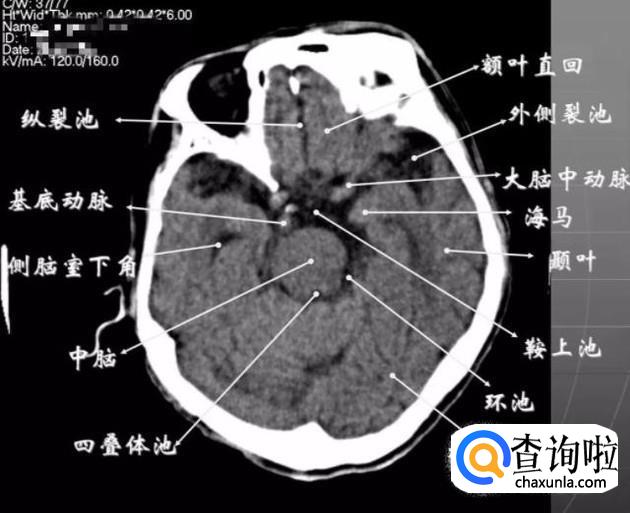

鞍上池层面

①颅前窝:颞叶。

② 鞍上池:在垂体窝上方,位于两侧颅中窝之间,前界为颞叶直回,侧方位颞叶海马,呈五角星形或六角星形。其前角连于纵裂池,两外侧角连于外侧裂池,两后外侧角延续于环池,第六个角位于后缘中间,是角间池。鞍上池边缘为大脑动脉环,池内前部常可见“v”字型视交叉。

③ 颅后窝:四脑室或四叠体池。